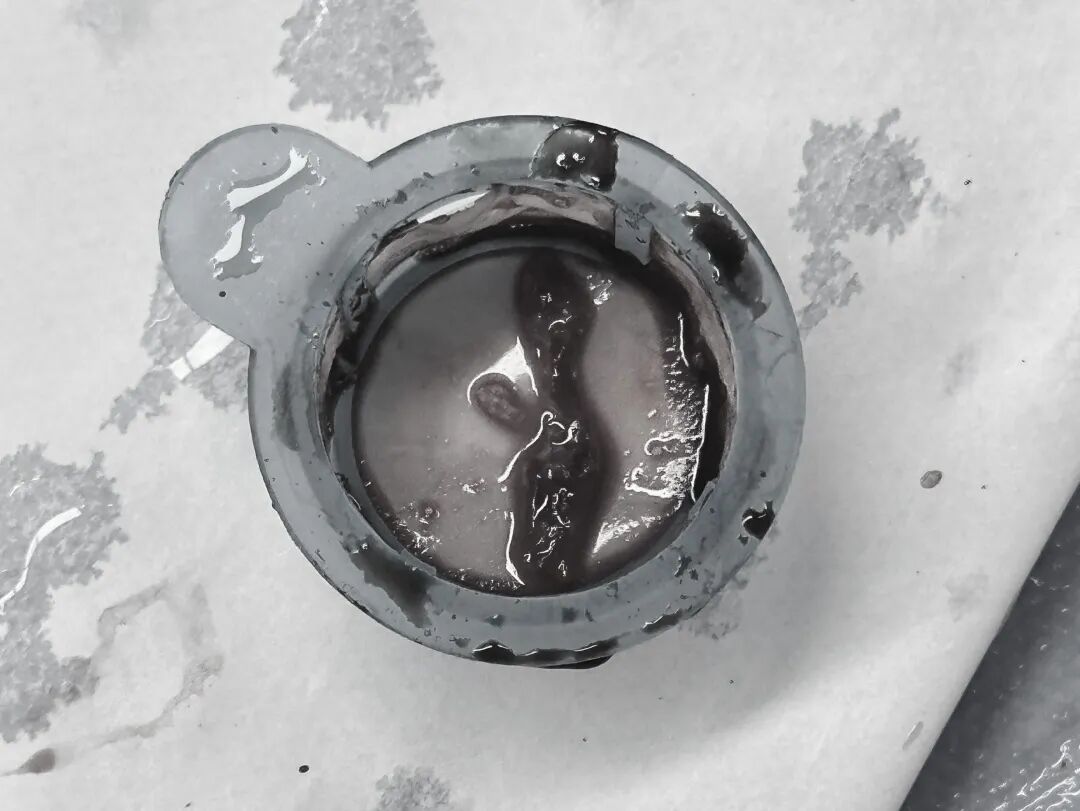

在手术过程中,患者突发心脏室速、室颤、电风暴等紧急情况,医护团队临危不乱,连续进行 4 次电除颤、电复律,最终成功抽出血栓,恢复血流。

考虑到患者年轻,团队采用了冠脉血栓抽吸+冠脉内药物溶栓方案,既挽救了生命,又避免了植入支架,为患者保留了更好的血管原始状态和远期预后。